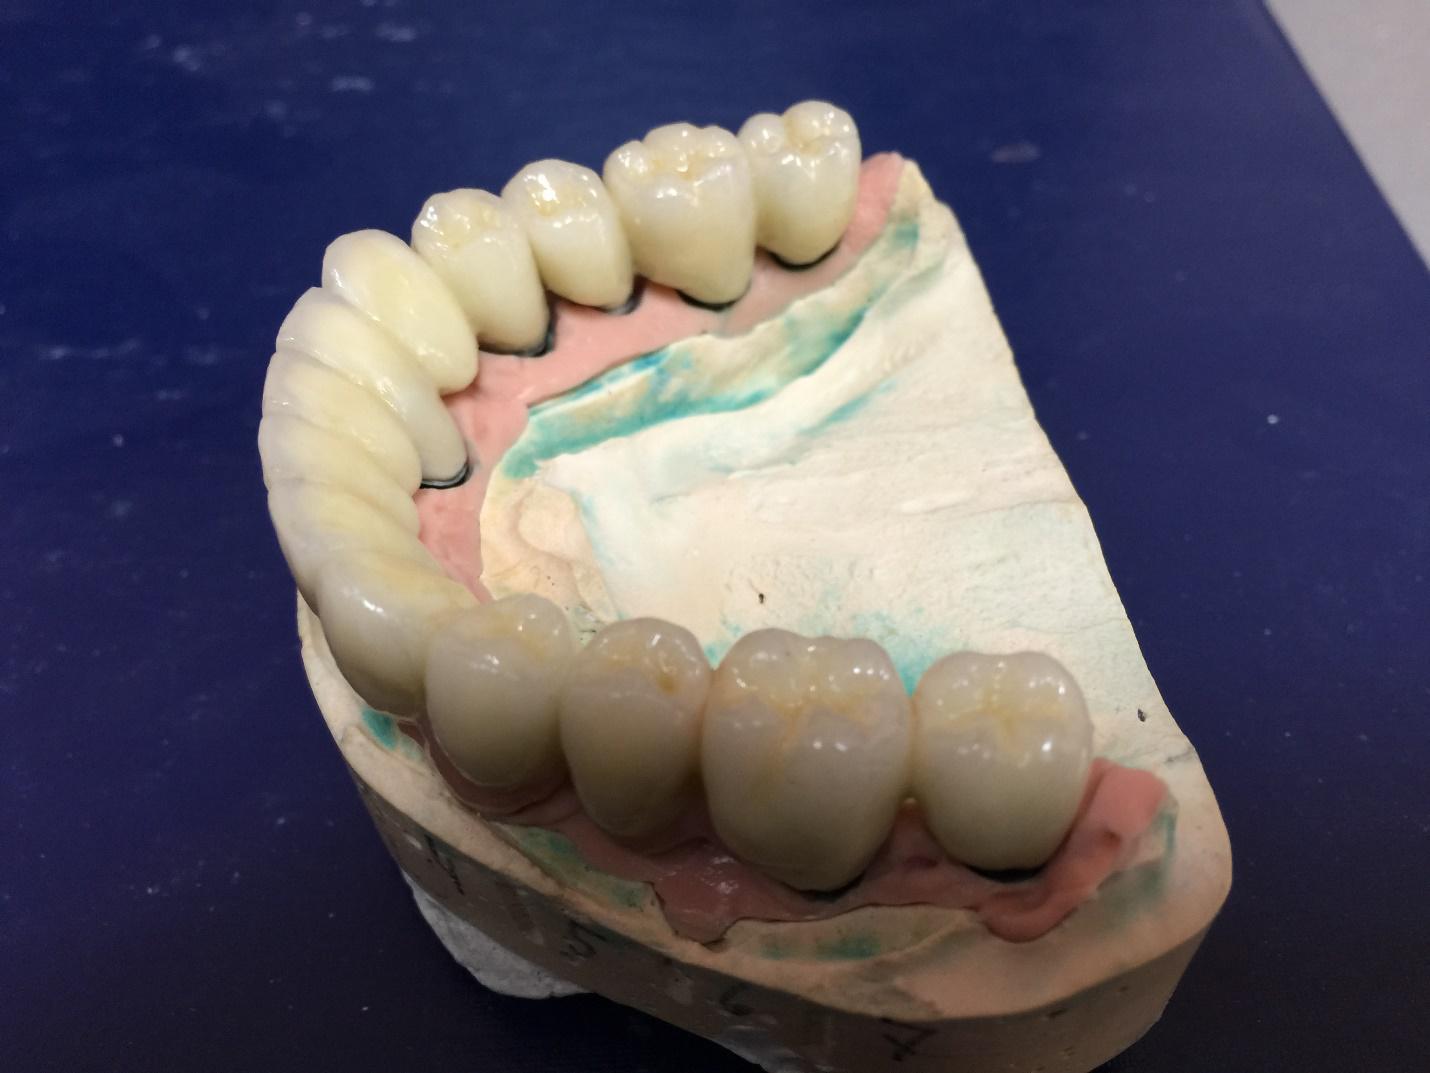

Ниже представлены фото аппарата и примеры работ: